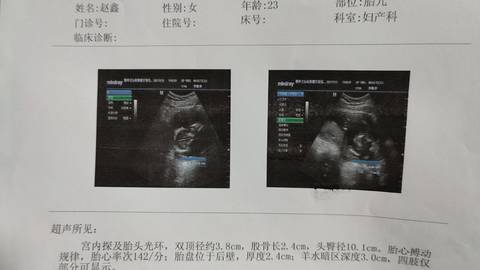

有没有宝妈会看的?这是男孩还是女孩啊?

journal_insert_pic_1678956718journal_insert_pic_1678956727

亲,我们都是一样觉得好奇,确实没什么依据,不要想太多,生下来最准确的,一切顺利!